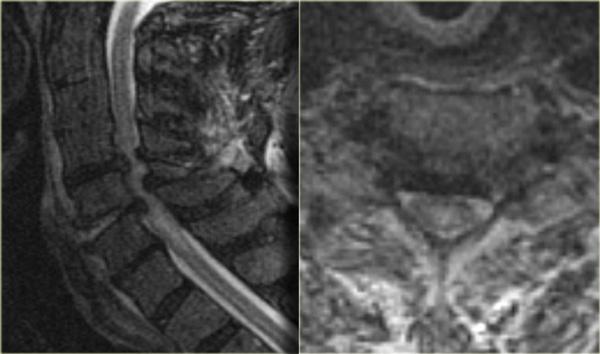

Bong gân tăng gấp (3)

MRI giải thích tình trạng thần kinh của bệnh nhân này.

Các dấu hiệu trên MRI bao gồm:

- Tổn thương mô mềm nặng nề ở các cấu trúc cạnh sống phía sau, đặc biệt tại mức C5-6, nơi dây chằng gian gai và dây chằng vàng bị đứt

- Rách đĩa đệm C5-6 với di lệch ra phía sau C5

- Phù nề tủy sống lan rộng

Tiếp tục với hình ảnh mặt cắt axial.

Hình ảnh axial cho thấy tổn thương tủy sống và ngoài ra còn có sự vắng mặt của khoảng trống dòng chảy (flow void) ở động mạch đốt sống phải.

Điều này gợi ý huyết khối do bóc tách động mạch.

Kết luận, bệnh nhân này không có gãy xương, nhưng có bong gân tăng gấp nặng kèm thoát vị đĩa đệm cấp tính, tổn thương tủy sống không xuất huyết và huyết khối động mạch đốt sống.

Chụp mạch cộng hưởng từ (MRA) xác nhận tắc nghẽn động mạch đốt sống phải.